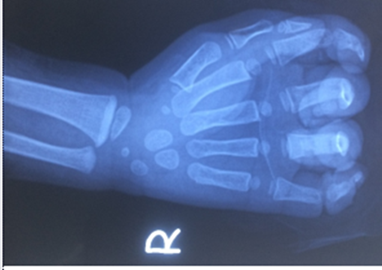

Bé trai nhập viện trong tình trạng chấn thương nặng bàn tay phải, đứt gân và đứt gần rời ngón thứ 5 do tay bị cuốn vào dây coroa máy rửa xe.